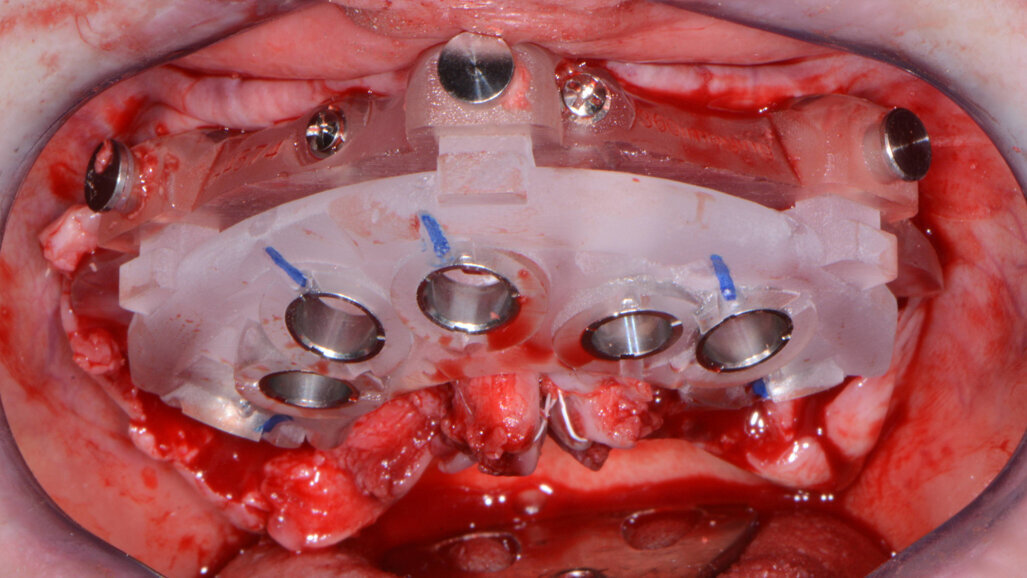

Once the virtual plan had been orchestrated by the laboratory and fully confirmed by me, the next appointment was for the planned surgery with all the necessary components for the guided surgical approach. The patient was appropriately sedated with intravenous medications, and local anaesthesia was administered in both arches. The tissue was then reflected using the Reflector instrument (GoldenDent) so that the bone levelling surgical guide would be fully seated and fixed with its respective retention screws (Figs. 6 & 7). After the positioning of the surgical guide, the maxillary teeth were atraumatically extracted from anterior to posterior utilising the Physics Forceps (GoldenDent). Using a bone reduction bur in the surgical handpiece and motor (Aseptico) with ample irrigation, the maxillary ridge was trimmed to the level indicated by the guide. Once the appropriate bone levelling had been accomplished with the surgical handpiece, the implant surgical guide (Fig. 8) was positioned into the bone levelling guide and the osteotomies for the implants were initiated with a designated pilot drill in the implant system’s guided surgery drilling kit (Adin Dental Implant Systems; Fig. 9).

Fig. 7: Maxillary bone levelling foundation guide.

Fig. 8: Maxillary implant surgical guide.